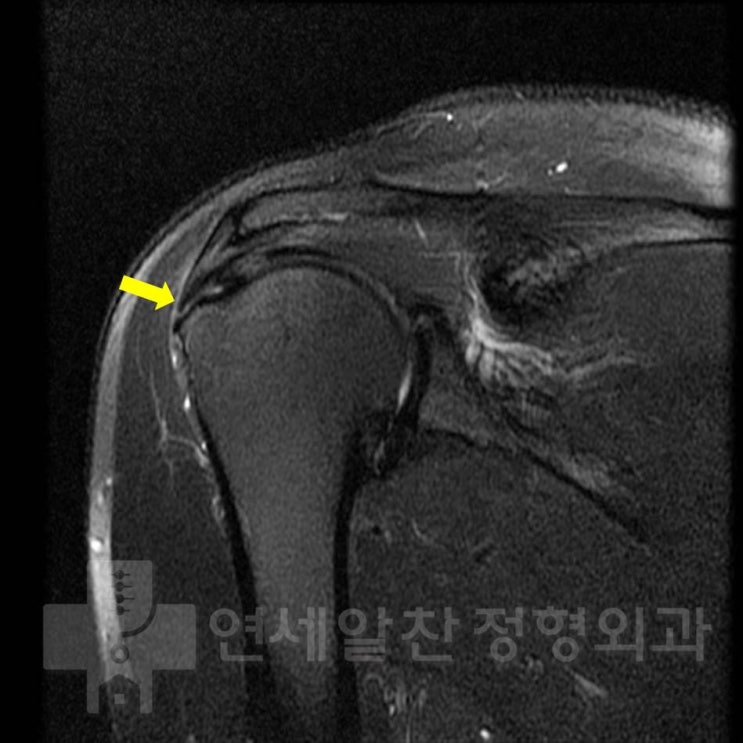

Rotator Cuff Repair (Supraspinatus Repair Using Double-Row Suture Bridge Technique)

#rotator cuff tear#supraspinatus tear#double-row suture bridge#rotator cuff repair#arthroscopy